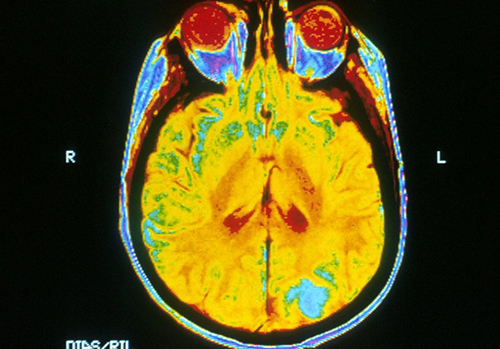

По их предположению, получение высокодетализированных изображений человеческого мозга возможно с использованием технологии из другой области. Речь идет о сейсмической томографии.

В отличие от имеющихся методов визуализации мозга, таких как МРТ, КТ и ПЭТ, технология может применяться для любого пациента с высокой частотностью. При этом устройство для получения данных относительно небольшое, что дает возможность более быстрой работы.

Исследователи уверены, что технология будет безопасной, поскольку звуковые волны уже используются для ультразвукового сканирования. Для этой технологии интенсивность звука на том же уровне. Однако ультразвук не может проникать сквозь кости, а новое устройство в виде шлема может преодолеть этот барьер.